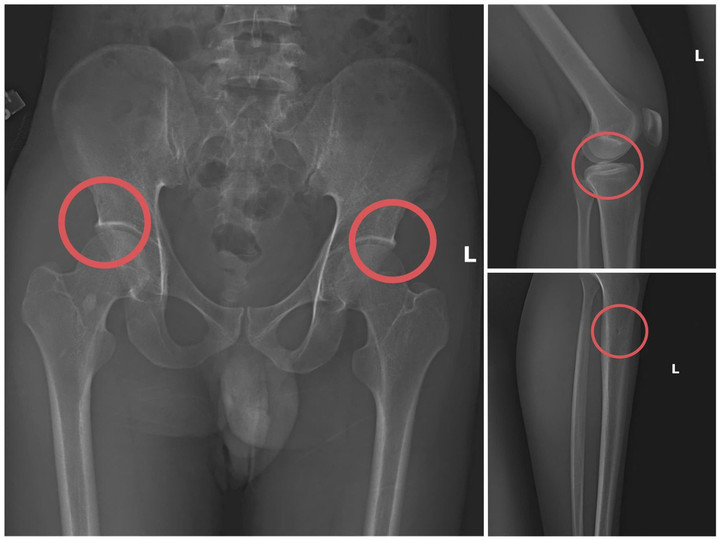

Cựu nhân viên y tế đục vỡ xương trục lợi bảo hiểm: Thủ đoạn tàn nhẫn, bất nhân- Ảnh 2.

Bản phim chụp XQ một số tổn thương xương do đối tượng tạo ra. (Ảnh: Công an tỉnh Phú Thọ).